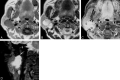

F<sc>ig</sc> 1.

Fig 1.

Case 1. A, Axial T1-weighted image (spin-echo: TR/TE, 650/10.7) shows a low-signal-intensity well-defined mass in the right parotid gland. B, Axial T2-weighted image (fast spin-echo: TR/TE, 3150/108) shows peripheral high signal intensity surrounding a central region of lower signal intensity.